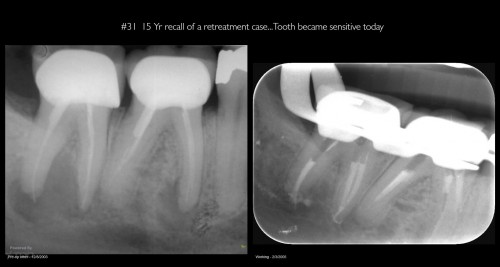

15 Yr Recall of a Retreatment case

By Gary Carr / August 13, 2018

Very compliant patient—always made his recalls. Tooth has been asymptomatic for 15 years…and the periapical […]